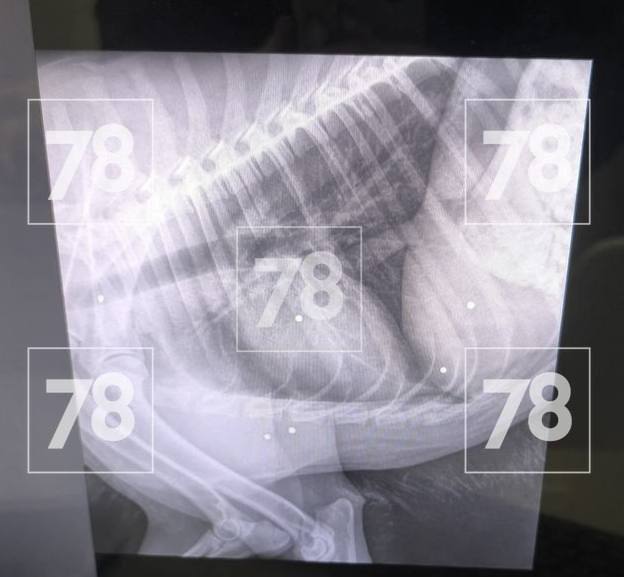

Рентген показал, что в животное выстрелили дробью. Врачи провели операцию, но вытащить смогли только три снаряда.